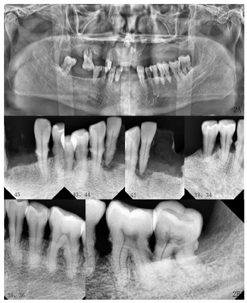

牙周专科检查示74%的位点PD≥3 mm,BOP为73%,牙龈呈暗红色,质脆,轻探出血。(图1)

影像学检查:曲面体层片及根尖片示13、16、42、38、48牙槽骨吸收至根尖;剩余牙牙槽骨吸收至根长1/2。CBCT示上颌正中多生牙,多生牙舌侧可见不规则低密度影像。(图2、图3)